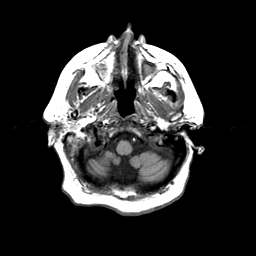

Basal Ganglia Calcification: T1-weighted MR -- Slice #2

[Home][Help][Clinical] Slice 2